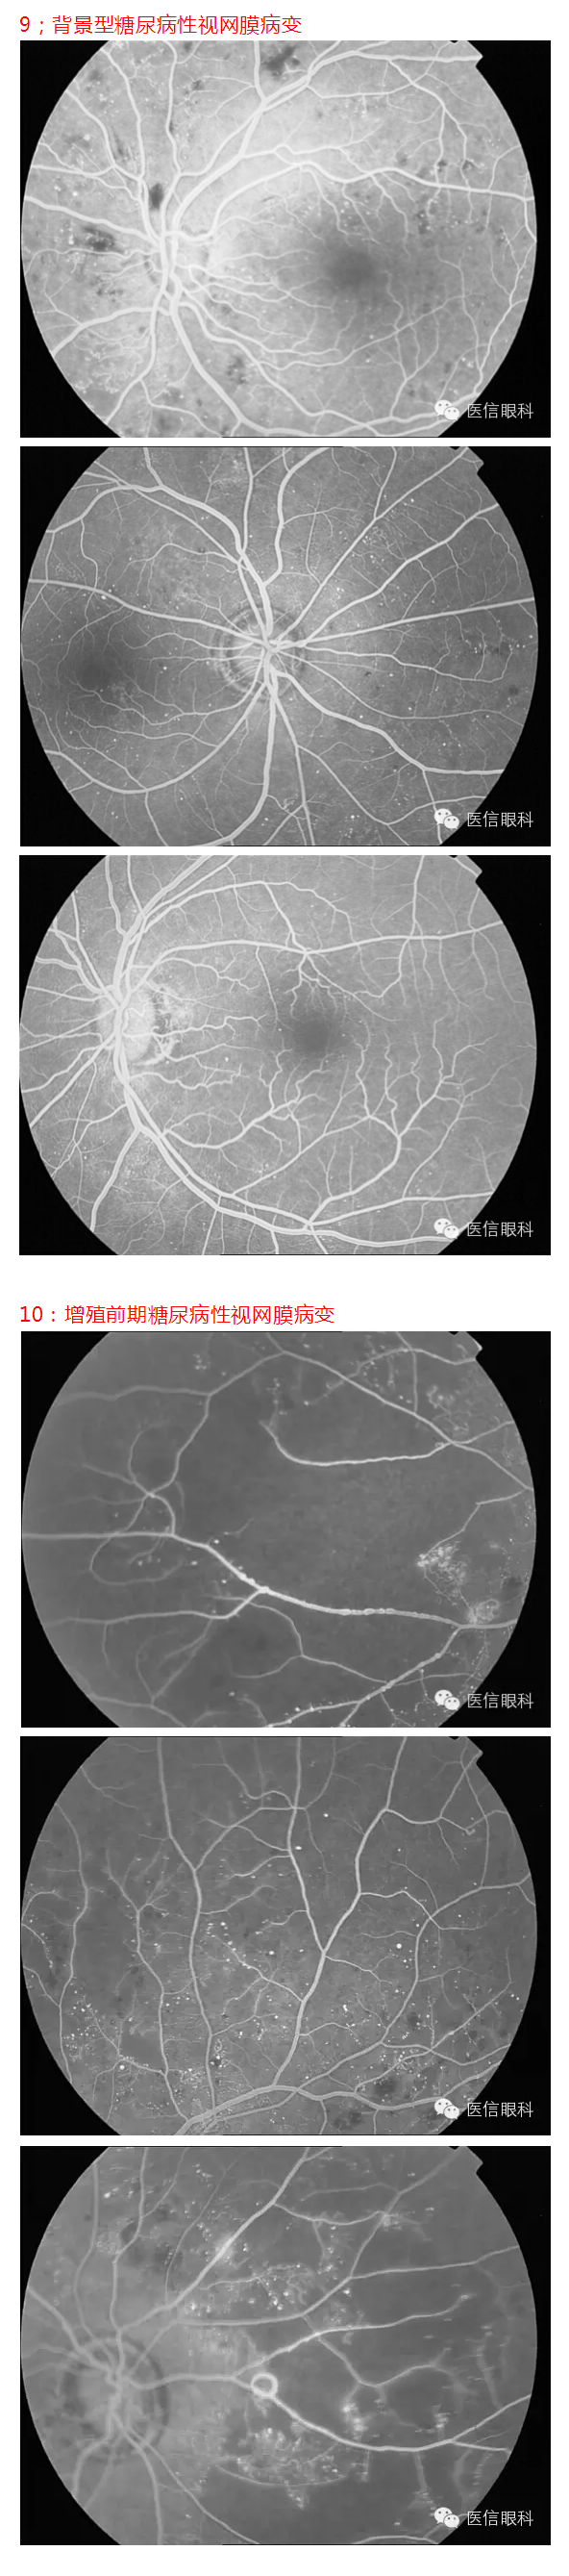

常见眼底病荧光血管造影表现(多图一)